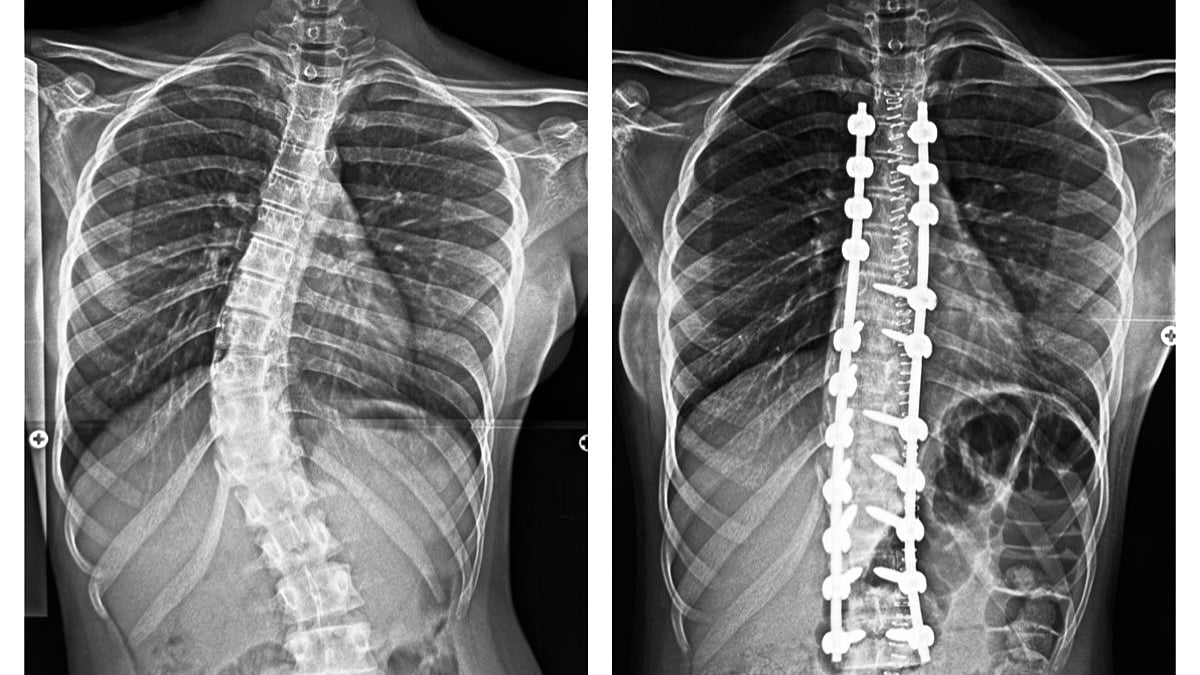

A 16-year-old schoolgirl regains posture and confidence after successful corrective scoliosis surgery at Wockhardt Hospitals, Mumbai | File Photo

Severe scoliosis, a condition where the spine curves abnormally like a bow, affects posture, breathing, and daily activities. At Wockhardt Hospitals, Mumbai Central, her spine curved across 12 vertebrae – nearly her entire backbone. Mild cases can be managed with observation or braces, but surgery was the only solution for her.

Under the supervision of Dr. Mazda Turel, Consultant Brain and Spine Surgeon at Wockhardt Hospitals, the surgery involved a midline incision, carefully placed screws and rods, and gradual correction of the twisted vertebrae. The meticulous procedure restored alignment, levelled her shoulders, and corrected her waist balance.